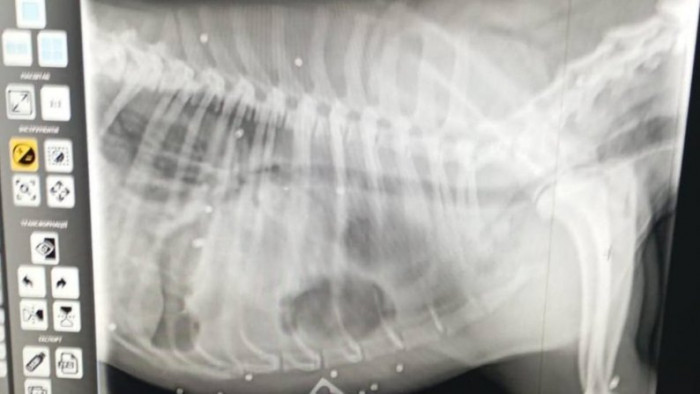

Рентген Біляша. Особистий архів Оксани

Біляш після поранення у ветклініці. Особистий архів Оксани"Ні. Це не дрон. Це дробь. Ну, воно ж видно. Він просто як решето був. Цілеспрямовано його розстрілювали. І зверху, і правий бік весь, і лапки".

Четвертого квітня Біляш повернувся до магазину, звідки зазвичай ніколи не відходив. Ірина згадує, на його тілі були рани, схожі на сліди пострілів з дробовика.